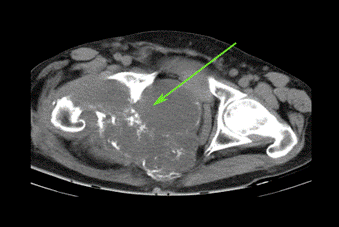

La Figura 2 muestra tomografía axial computarizada (TAC) realizada, donde se apreció imagen tumoral mixta en hemipelvis derecha que invadió y desplazó los órganos de la cavidad.